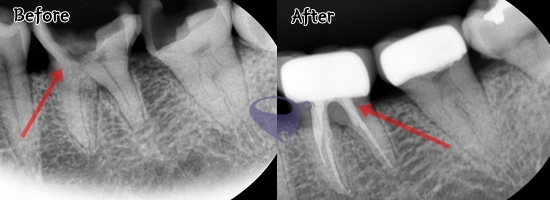

신경치료는 충치가 치수 조직까지

감염시켰을 때 진행하게 되는데요.